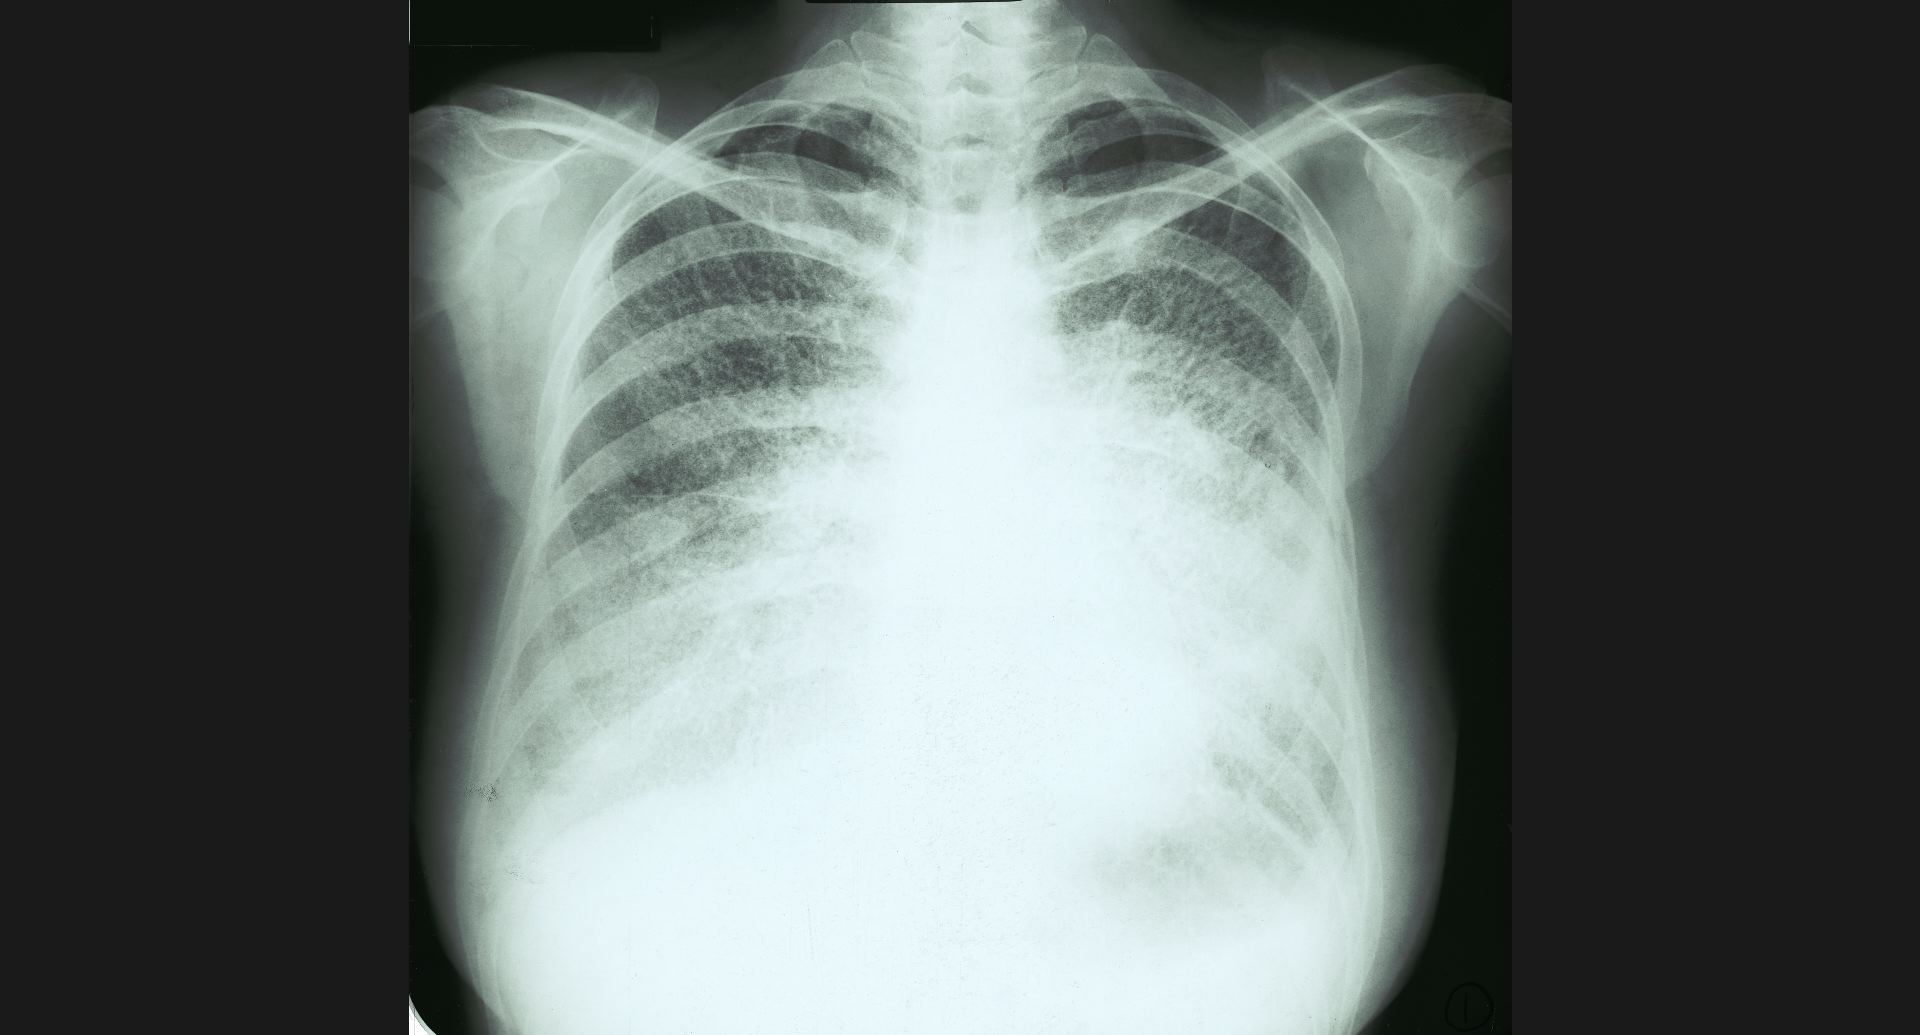

fig.5(93KB) :Post-plomboge chest

ピンポン玉、左肺上葉の細かい石灰巣。